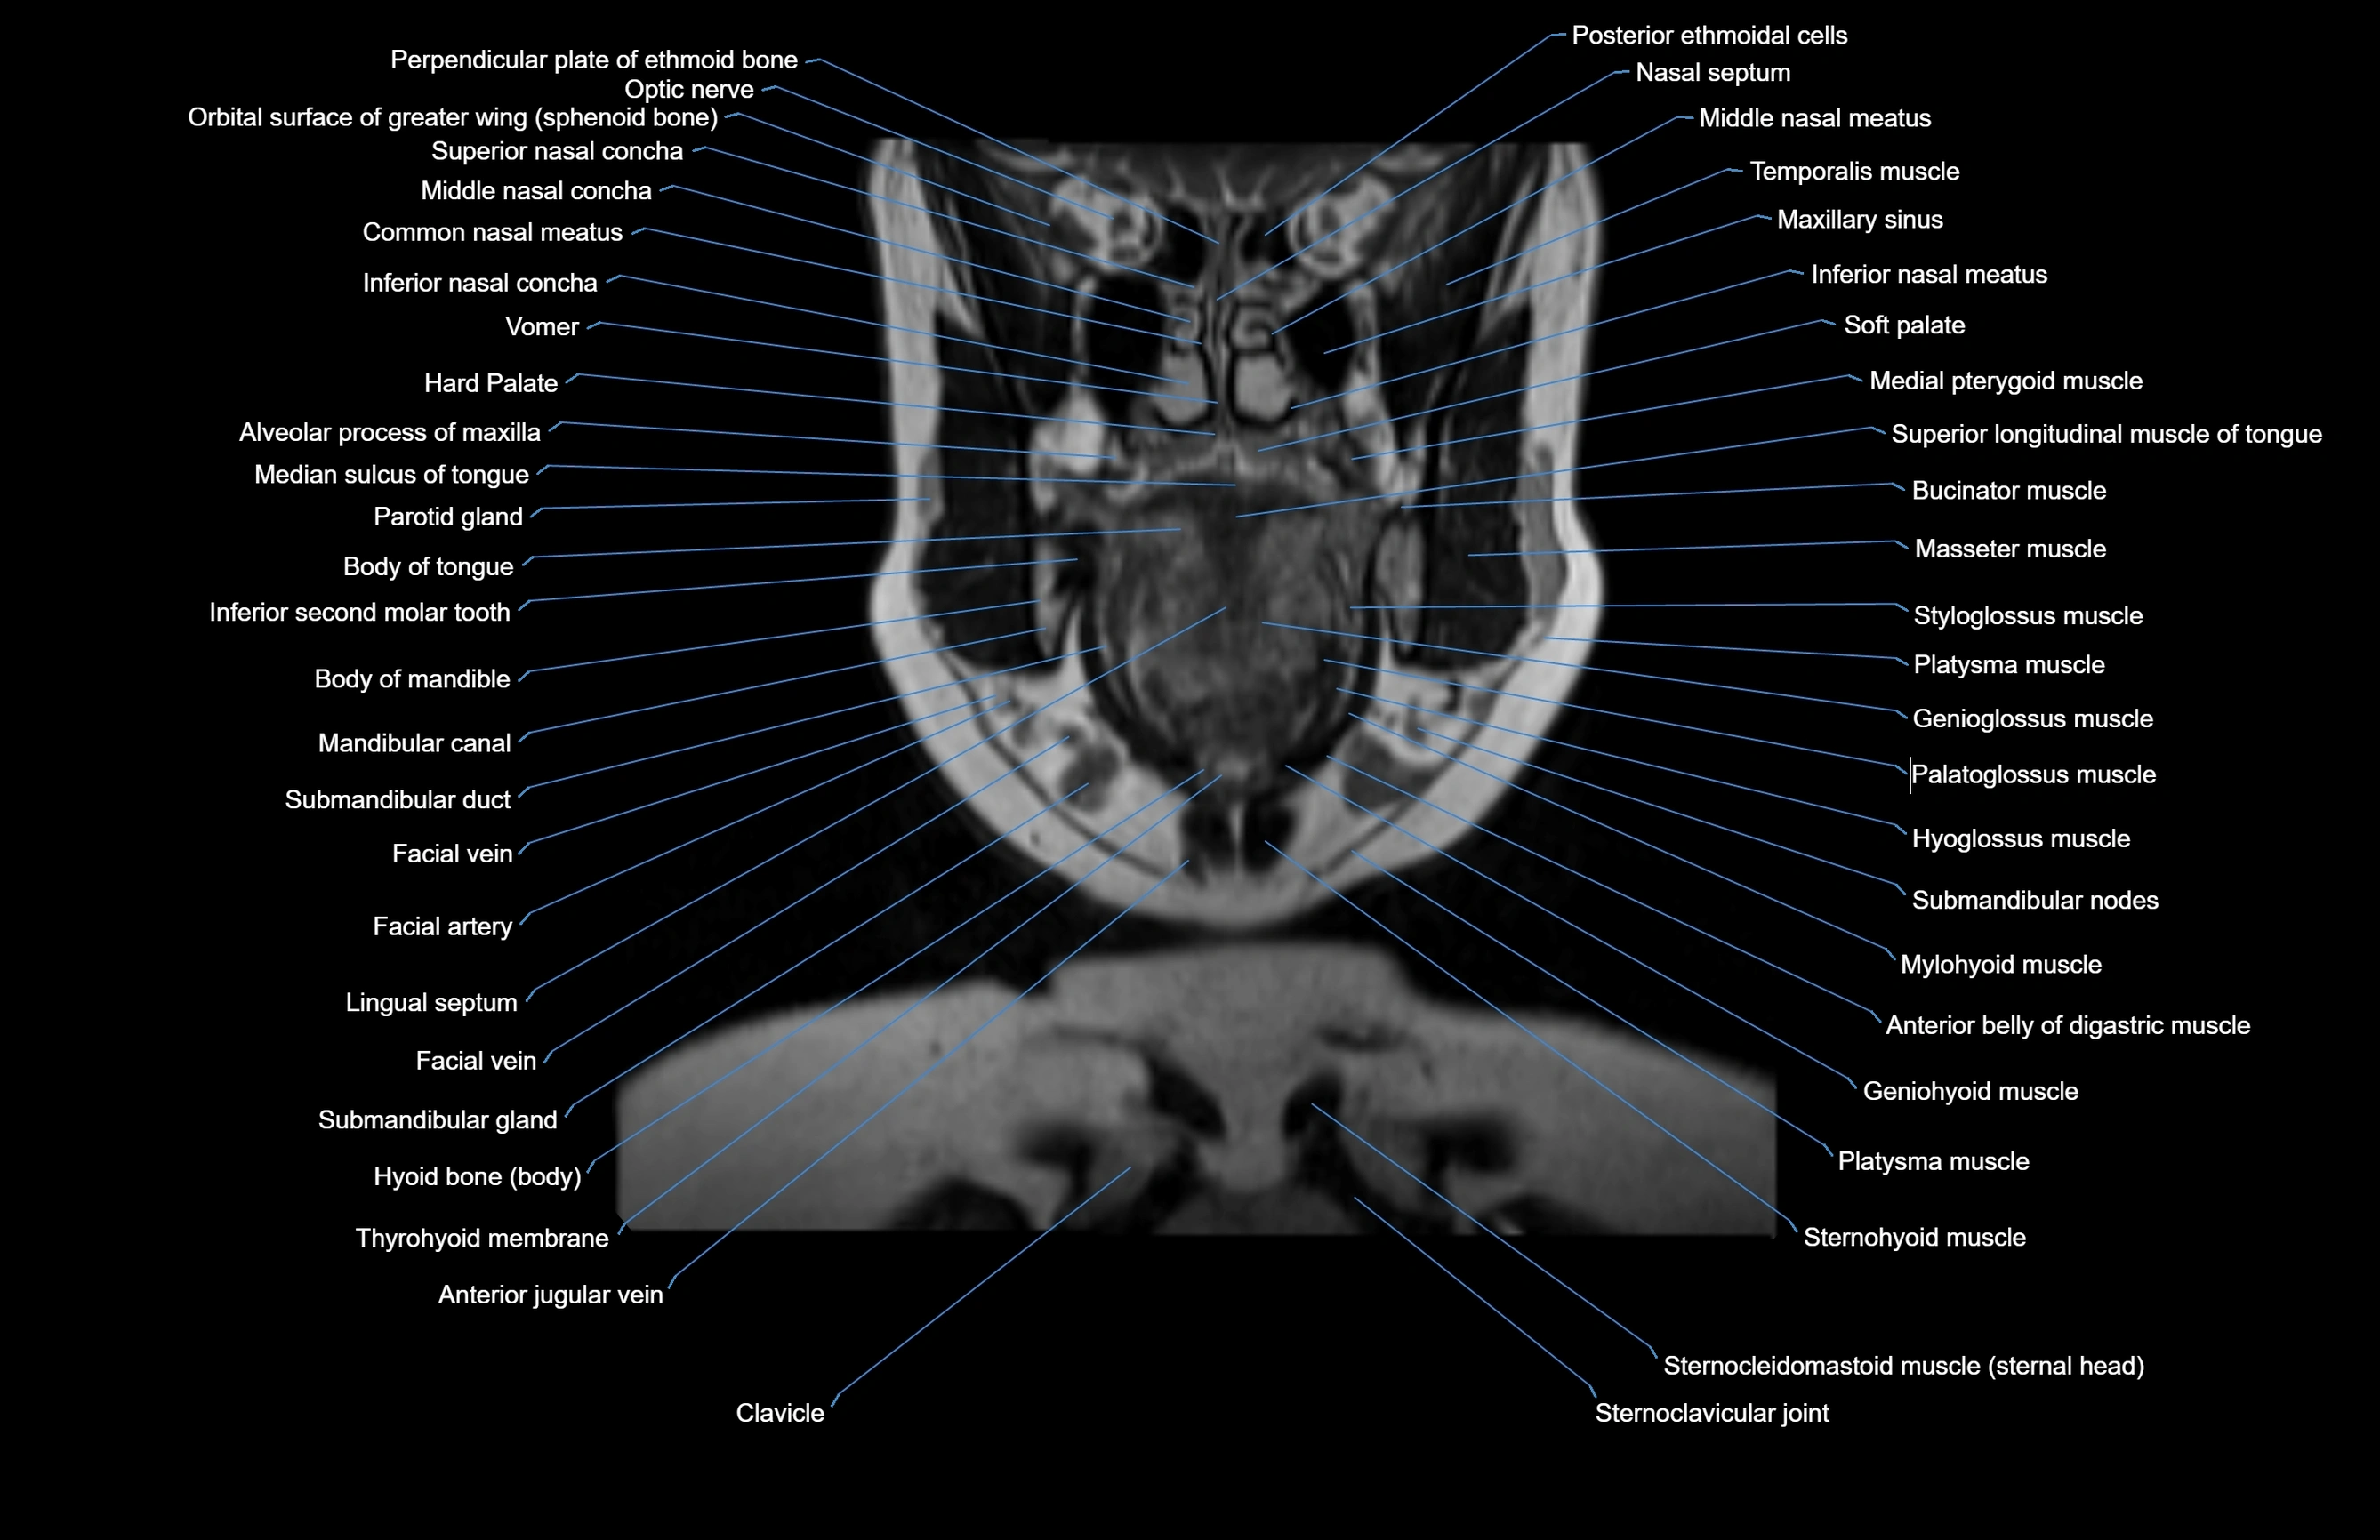

- Alveolar process of maxilla

- Body of mandible

- Body of tongue

- Common nasal meatus

- Genioglossus muscle

- Hard palate

- Hyoglossus muscle

- Inferior nasal concha

- Inferior nasal meatus

- Lingual Septum

- Mandibular canal

- Masseter muscle

- Medial pterygoid muscle

- Middle nasal concha

- Mylohyoid muscle

- Nasal septum

- Palatoglossus muscle

- Platysma muscle

- Soft palate

- Sternohyoid muscle

- Sternocleidomastoid muscle

- Submandibular duct

- Submandibular gland

- Submandibular lymph nodes